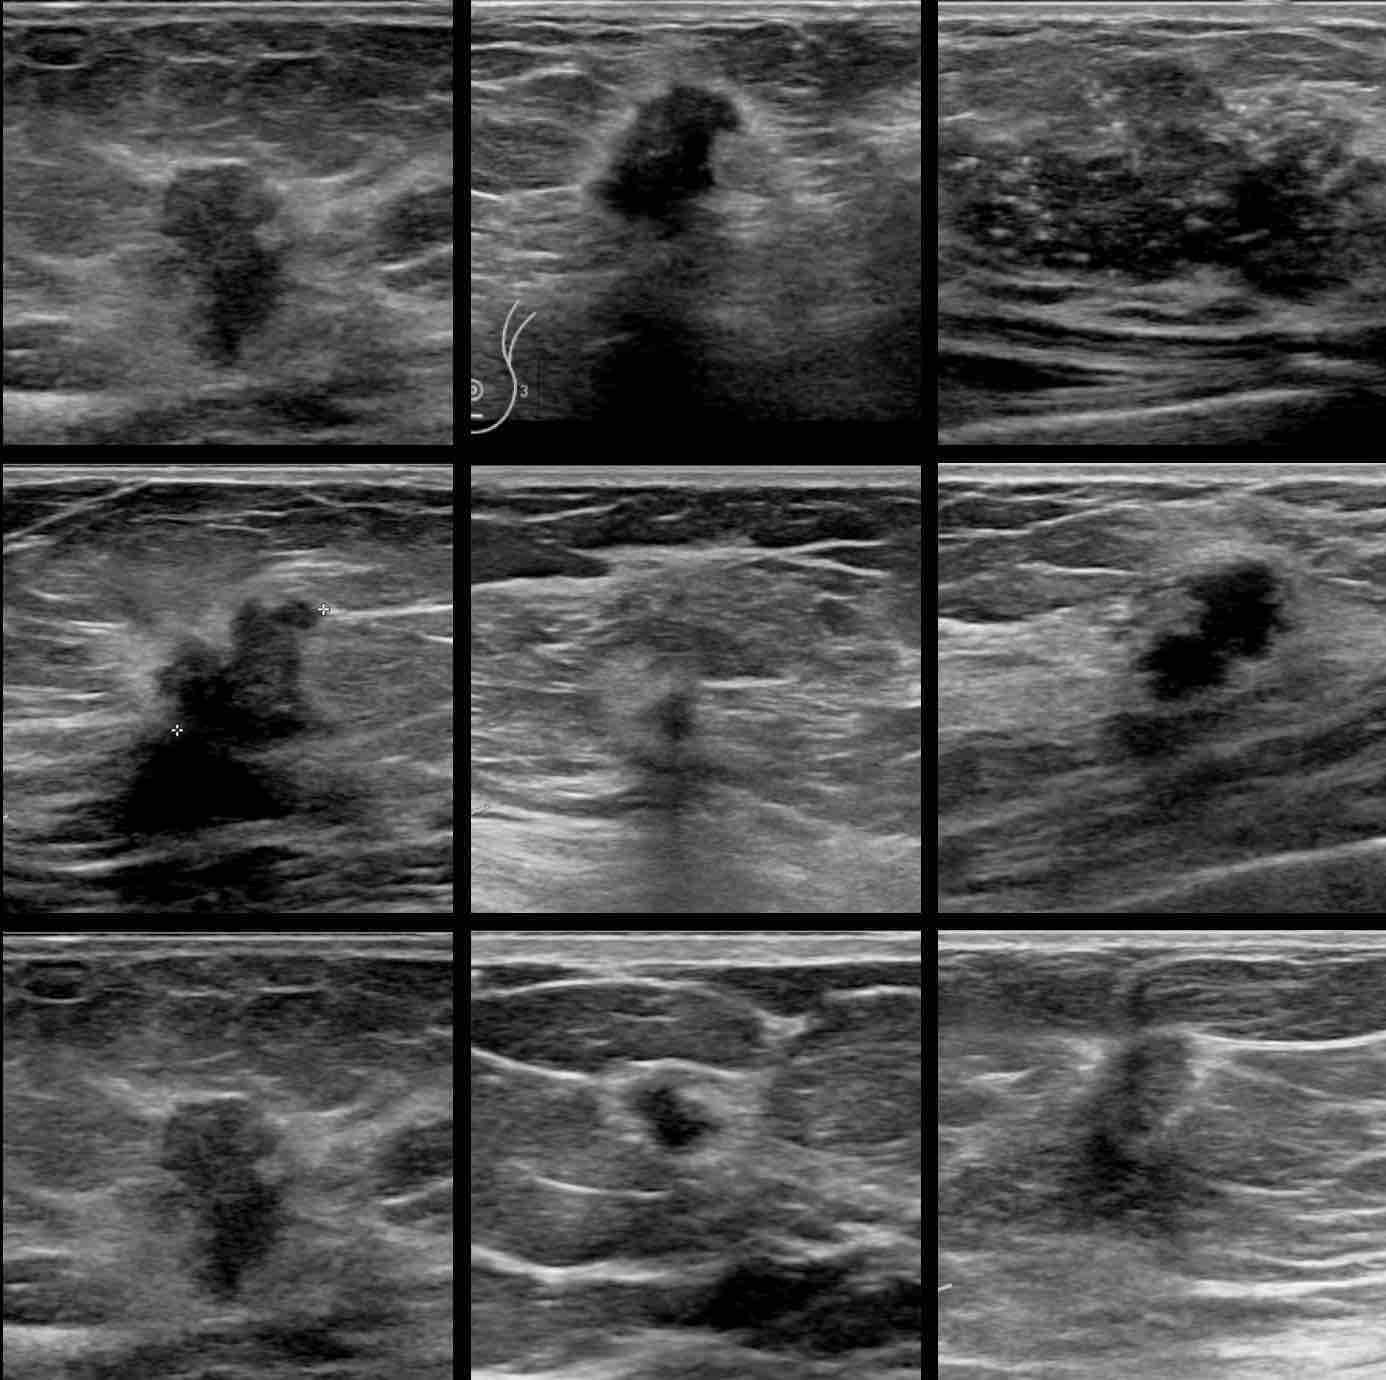

Dưới đây là một số ví dụ về ung thư vú.

Các đặc điểm chính bao gồm:

- Khối giảm âm

- Hình dạng thường không đều – đôi khi tròn hoặc bầu dục với hướng không song song với da

- Bờ không rõ, đôi khi có quầng sáng (halo)

- Có thể có bóng cản phía sau và các vôi hóa nhỏ

Các ví dụ về ung thư vú

Cuộn qua mười một ví dụ về ung thư vú đã được xác nhận bằng sinh thiết.